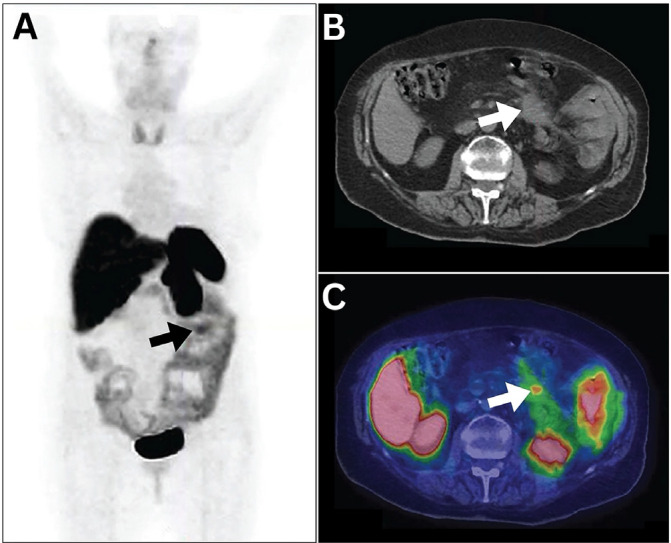

本系统综述旨在探讨目前报道的镓-68 (68Ga)- 1,4,7,10 -四氮杂环十二烷- 1,4,7,10 -四乙酸tyr3 -奥曲肽(68Ga- dotatoc)的假阳性结果。使用PubMed, Web of Science和Scopus数据库进行系统搜索,并更新至2024年3月4日。三位作者独立筛选检索文章的标题和摘要,并根据纳入和排除标准选择文章。在对涉及601例患者的42篇纳入的研究文章的定性分析中,确定并分类了219例假阳性结果。非肿瘤病因占多数,占50.2%,其次是良性肿瘤(27.4%)和恶性肿瘤(22.4%)。解剖学上,腹部是最常见的陷阱部位(30.6%),其次是肌肉骨骼(22.4%)、头颈(20.5%)和骨盆(14.6%)区域。胸部最不常见,仅占11.9%。本研究阐明了潜在的假阳性结果,主要发生在腹部和头颈部区域-脑膜瘤和神经内分泌肿瘤(NETs)的原发部位。了解这些假阳性结果对于准确诊断至关重要。此外,认识到这些缺陷可能会导致68Ga-DOTATOC在评估神经网络和脑膜瘤的传统用途之外的新应用,潜在地扩大其目前的用途。

This systematic review aimed to explore the currently reported false positive findings of Gallium-68 (68Ga)-1, 4, 7, 10-tetraazacyclododecane-1, 4, 7, 10-tetraacetic acid Tyr3-octreotide (68Ga-DOTATOC). PubMed, Web of Science, and Scopus databases were used to conduct a systematic search and were updated until March 4, 2024. Three authors independently screened the titles and abstracts of the retrieved articles and selected the articles based on the inclusion and exclusion criteria. In a qualitative analysis of 42 included research articles involving 601 patients, 219 false positive findings were identified and categorized. Non-oncologic etiologies predominated, constituting 50.2% of pitfalls, followed by benign oncologic (27.4%) and malignant neoplasms (22.4%). Anatomically, the abdomen was the most common site for pitfalls (30.6%), followed by the musculoskeletal (22.4%), head and neck (20.5%), and pelvic (14.6%) regions. Chest region findings were least frequent, accounting for only 11.9%. This study elucidates potential false positive findings, predominantly occurring in the abdominal and head-neck regions-primary sites for meningiomas and neuroendocrine tumors (NETs). Understanding these false-positive findings is crucial for accurate diagnosis. Furthermore, recognizing these pitfalls may lead to novel applications of 68Ga-DOTATOC beyond its conventional use in evaluating NETs and meningiomas, potentially expanding its current utility.